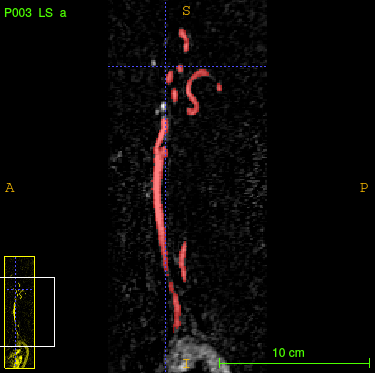

The backprojection operator causes a kind of shroud (Figure 3.1), so we have to think about a filtrated backprojection. Therefore, we apply a convolutional layer before backprojection. Using filters, which get adapted during training for each projection direction individually, leads to a more satisfying result (Figure 3.1).

\phantomcaption